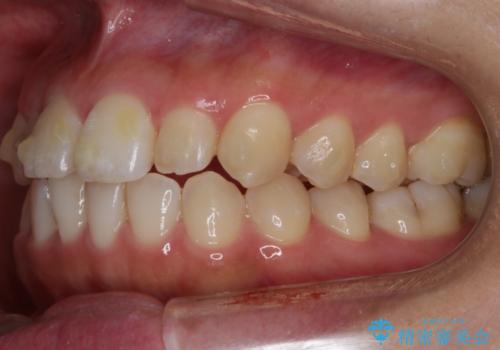

【非抜歯】部分矯正でも治る 前歯の反対咬合

- 前歯にガタつきを主訴にご来院されました。

奥歯の嚙み合わせに問題がほとんどみられなかったため、インビザライン ライトパッケージでの部分矯正を行うこととなりました。

今回のケースでは奥歯の噛み合わせに問題がほぼみられなかったため、前歯の位置のみに焦点を当て部分矯正を行いました。